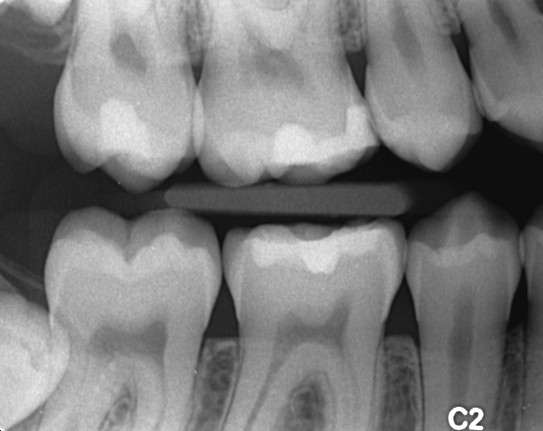

Et mesterstykke i bedrag. Deans undersøgelser fra 1942 af sammenhængene mellem caries, fluor og dental fluorose i 13 amerikanske byer. Af uransagelige årsager er 0-punktet for fluorose henlagt til en cariesforekomst på 3 DMF-T. Herved opnås et skæringspunkt mellem de to linier svarende til et fluoridindhold i drikkevandet på 1 ppm (det såkaldt optimale fluorindhold). Ingen af byerne havde en gennemsnitlig DMF-T blandt 12 til 14 årige på mindre end 2. I dagens Danmark betragtes dette som en meget høj cariesforekomst. Årsagen er at mundhygiejnen i USA i 1942 var ekstrem dårlig, en faktor som der slet ikke er taget højde for.